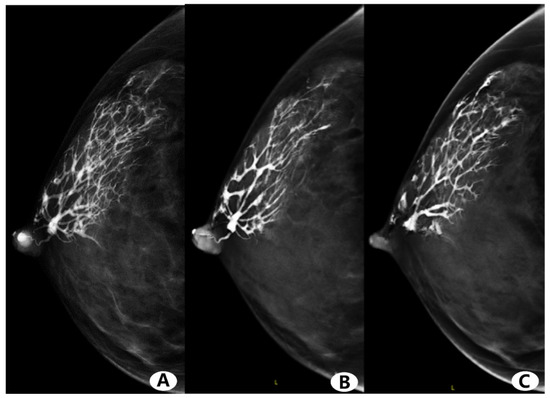

3.3. Visual Image Analysis

3.4. Imaging Finding